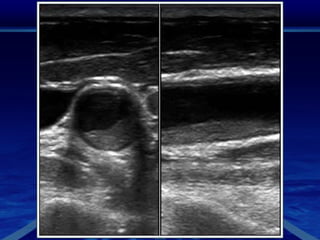

Ultrasonido CarotideoEl ultrasonido Doppler es el método de imagen más utilizado en el estudio de las carótidas Ofrece una evaluación no invasiva para detectar las placas de ateroma como causa de tromboembolismocerebral.Permite definir sus características y el grado de estenosis que producen, muchas  veces constituye el único estudio antes de la cirugía o la colocación de stent.

En el estudio de las carótidas, se estudian las arterias carótidas, los grandes vasos del cuello que llevan la sangre al cerebro. La ecografía carotidea puede mostrar placas que estrechen la arteria y reduzcan el flujo de sangre que llega al cerebro.la ecografía no conlleva exposición a radiación ionizante, lo que significa que puede repetirse la exploración sin preocupación por la acumulación de radiación. Además, ultrasonidos de carótida es una técnica en tiempo real que nos indica como está el flujo sanguíneo en el momento de realizarse la exploración.

Ultrasonido CarotideoEl ultrasonidoDoppler es el método de imagen más utilizado en el estudio de las carótidas Ofrece una evaluación no invasiva para detectar las placas de ateroma como causa de tromboembolismocerebral.Permite definir sus características y el grado de estenosis que producen, muchas  veces constituye el único estudio antes de la cirugía o la colocación de stent.

En el estudiode las carótidas, se estudian las arterias carótidas, los grandes vasos del cuello que llevan la sangre al cerebro. La ecografía carotidea puede mostrar placas que estrechen la arteria y reduzcan el flujo de sangre que llega al cerebro.la ecografía no conlleva exposición a radiación ionizante, lo que significa que puede repetirse la exploración sin preocupación por la acumulación de radiación. Además, ultrasonidos de carótida es una técnica en tiempo real que nos indica como está el flujo sanguíneo en el momento de realizarse la exploración.